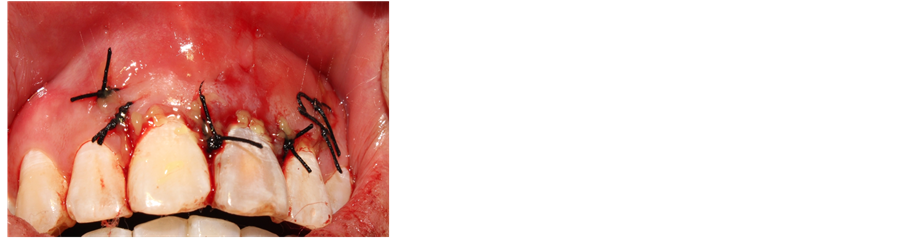

mm (Figures 4-6). 3) Scratch the apex and wash it with normal saline. Restore and suture the mandibular with minocycline smeared in partial (Figure 7). 4) Post-operative CBCT shows that root filling was improved and the resistant projection of agglomerate at apex disappeared (Figures 8-9). 5) Fistula disappeared 1 week after operation (Figure 10). 6) Intracoronal bleaching was conducted and then medical prescription was changed twice in follow-up visit. The color of 21st tooth became 11 and 12 with resin repair at the incisal margin of 21st tooth. 7) The color change of bleaching opisthosoma is relatively obvious than that in neck. The color of tooth neck is dark. The protective screen was established for the third bleaching. Four days later, further consultation was conducted with color of tooth neck improved. The patient was satisfied (Figure 11). 8) 1, 3, 6 and 12 months after operation, further consultation was conducted in follow-up (Figure 12).

Figure 7. Suturing reattachment.